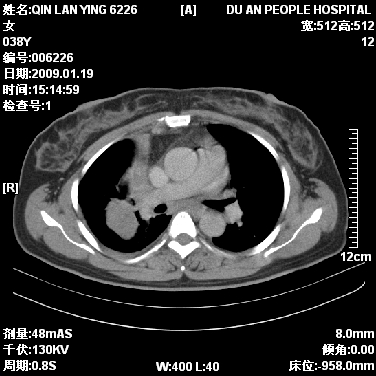

女,38岁,胸疼1个月。wbc:1万4

考虑----右肺中心型肺癌---阻塞性肺炎-----纵膈淋巴结及胸膜转移----肝脏转移

右肺中心型肺癌纵膈淋巴结转移,肝脏转移。右侧胸腔少量积液。

1)右肺中央型肺癌并右肺上叶阻塞性肺炎、节段性肺不张,纵隔淋巴结转移、右侧胸膜转移、肝脏转移。2)右侧胸腔少量积液。

1、右侧中央型肺癌并阻塞性肺不张,纵隔内、主动脉弓旁、右肺门淋巴结及肝脏转移可能性大,建议纤支镜进一步检查。

2、右侧胸腔积液。

本病例有几个容易诊断的地方:1、右肺上叶前段支气管闭塞,肺不张。2、淋巴结明显肿大。3、肝脏多个类圆形低密度影呈“牛眼征”改变,高度提示转移。

从影像学角度分析      右肺上叶中央型肺癌,并阻塞性不张、肺炎,纵隔淋巴结、膈顶淋巴结转移。

肝内两个大小不等低密度结节,内可见更低密度影,首先考虑肝内转移瘤,但联想到患者wbc1万4,建议楼主还是做个增强比较明确,除外肝脓肿的可能。